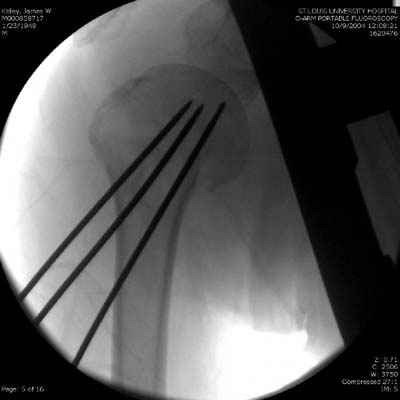

Здесь случай перелома-вывиха плеча, больному 56 лет, после "дважды" закрытой неудачной репозиции, опять же ургентно взяли в операционную, после полного общего обезболивания попытались сделать репозицию, и фиксацию провели спицами.

Больной находился в повязке, примерно напоминяющей косыночную, рекомендованы движения в локтевом суставе и маятниковые движения в плече, спицы удалены в три недели (были случаи миграции)